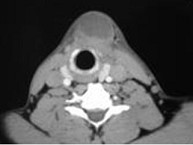

6.CT檢查結果見下圖,本患者應考慮為  (    )